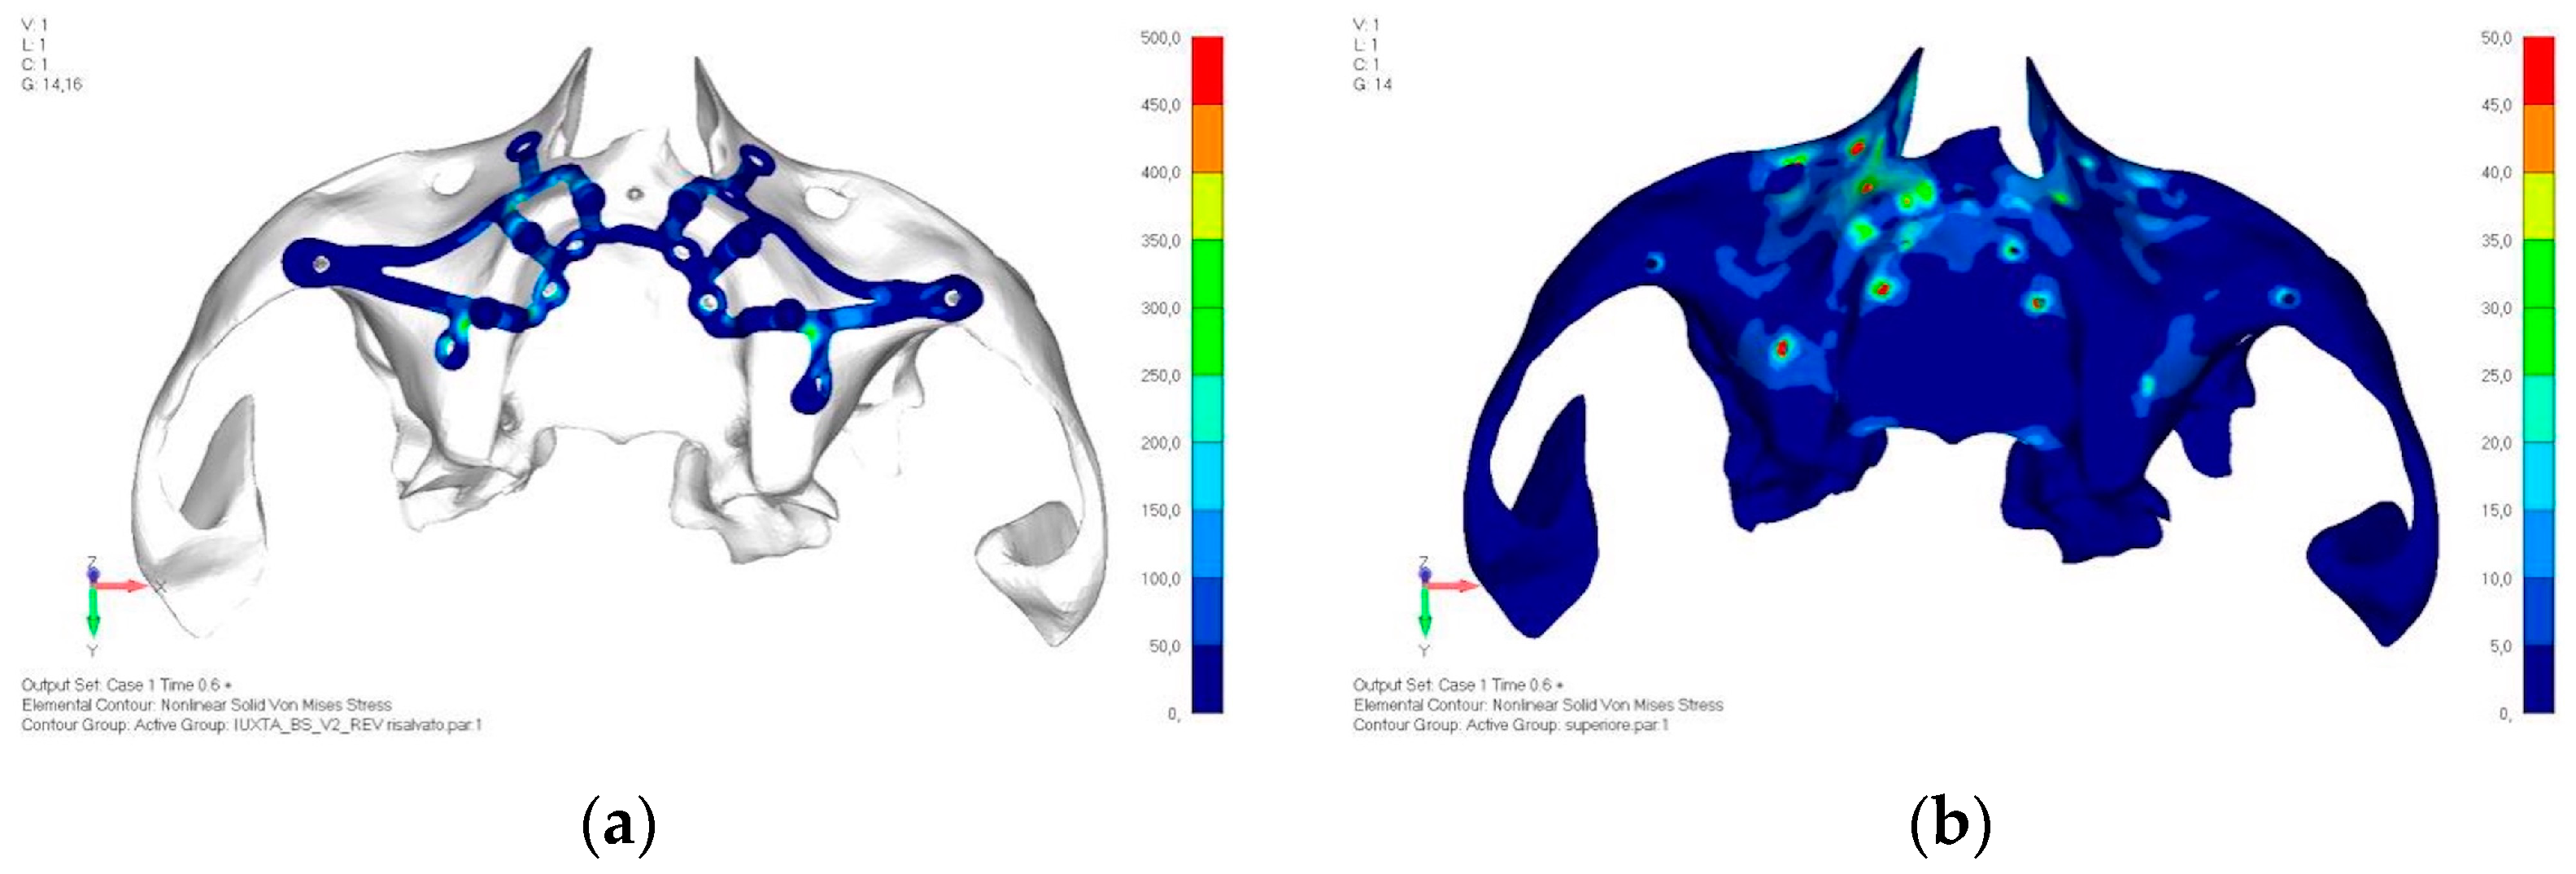

- Model V2. This model serves as an alternative to model V1, as it aims to stabilize the structure posteriorly using screws placed in the vestibular direction rather than the palatal direction (Figure 10). The model displayed similar behavior to V1, leading to the decision to proceed with V1 for further development (Figure 11a,b).